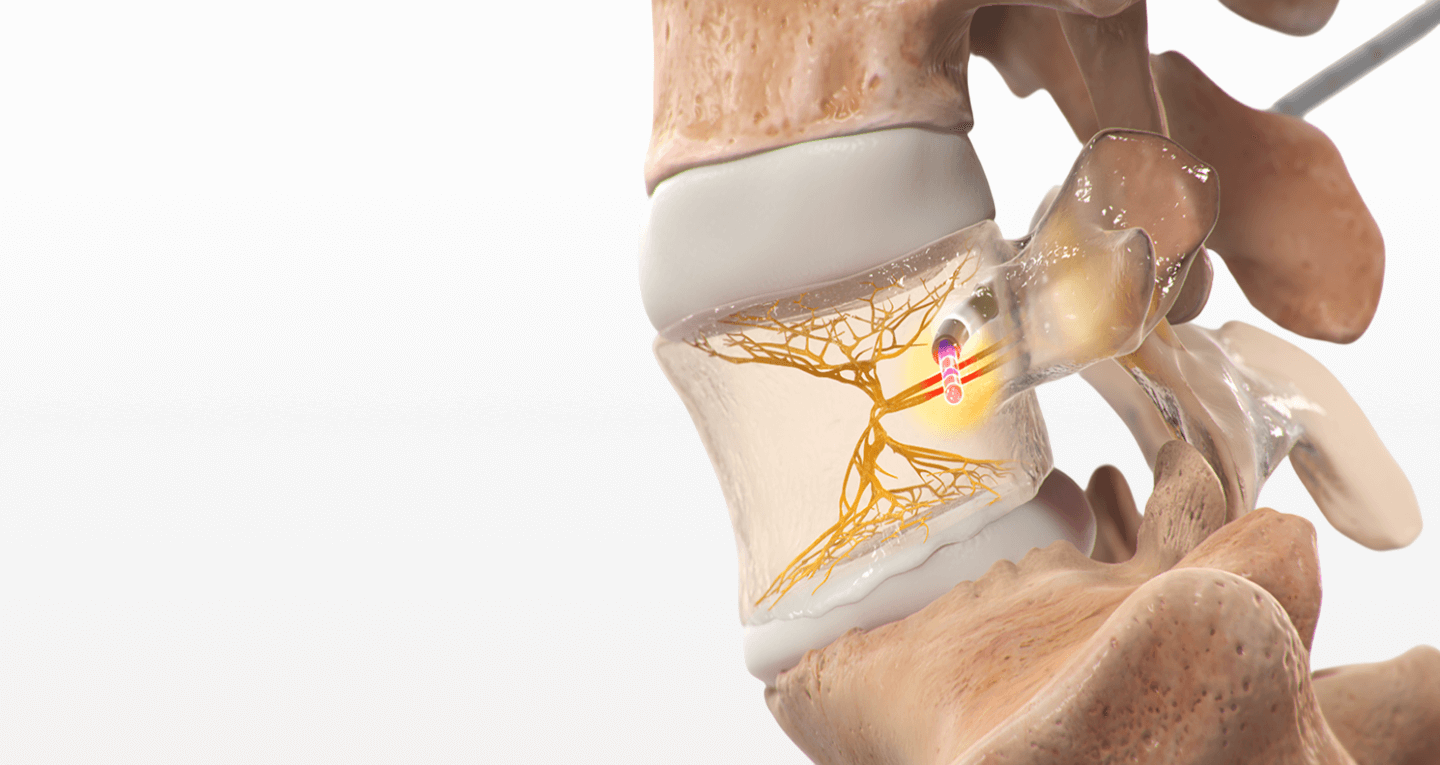

The Intracept® Procedure is a minimally invasive treatment specifically designed for chronic low back pain caused by vertebrogenic pain—a condition linked to damage in the vertebral endplates. These endplates, located between the spinal discs and vertebrae, can become irritated over time, triggering pain signals through a nerve called the basivertebral nerve. Intracept® works by using radiofrequency energy to precisely target and disable the basivertebral nerve, stopping it from sending pain signals to the brain.

What Happens During the Intracept® Procedure?

While you’re under anesthesia and lying on your stomach, your provider will:

1. Make a small incision in your back.

2. Use X-ray guidance to insert a narrow tube into the vertebra.

3. Create a pathway to the basivertebral nerve.

4. Insert a radiofrequency probe into the nerve.

5. Apply heat to ablate (disable) the nerve.

6. Remove the instruments and close the incision with sutures.